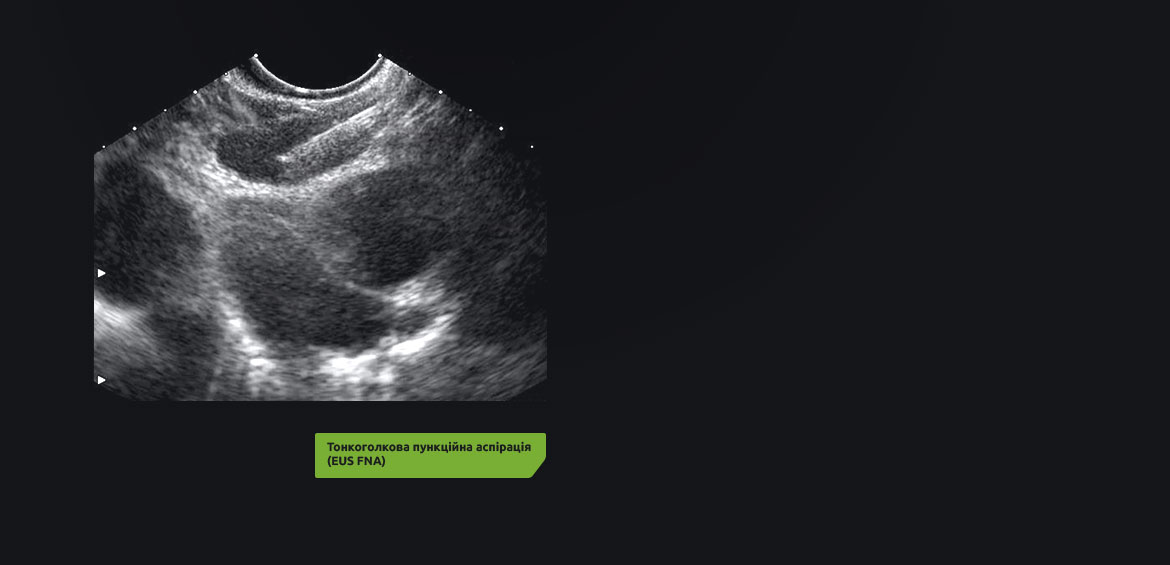

Завдяки високій роздільчій здатності цифрової ультразвукової системи High-Resolution EUS стало можливим більш точне виявлення та визначення стадії захворювання при дослідженні медіастинальних лімфатичних вузлів за допомогою тонкоголкової пункційної біопсії/аспірації (EUS FNB/FNA). Можливість використання ультразвукової ендоскопії стравоходу і ендобронхіального ультразвукового дослідження допомагає лікареві максимально точно діагностувати ступінь захворювання.

• Безпечне позиціонування голки для тонкоголкової пункційної біопсії/аспірації (FNВ/FNA) під контролем ультразвуку.